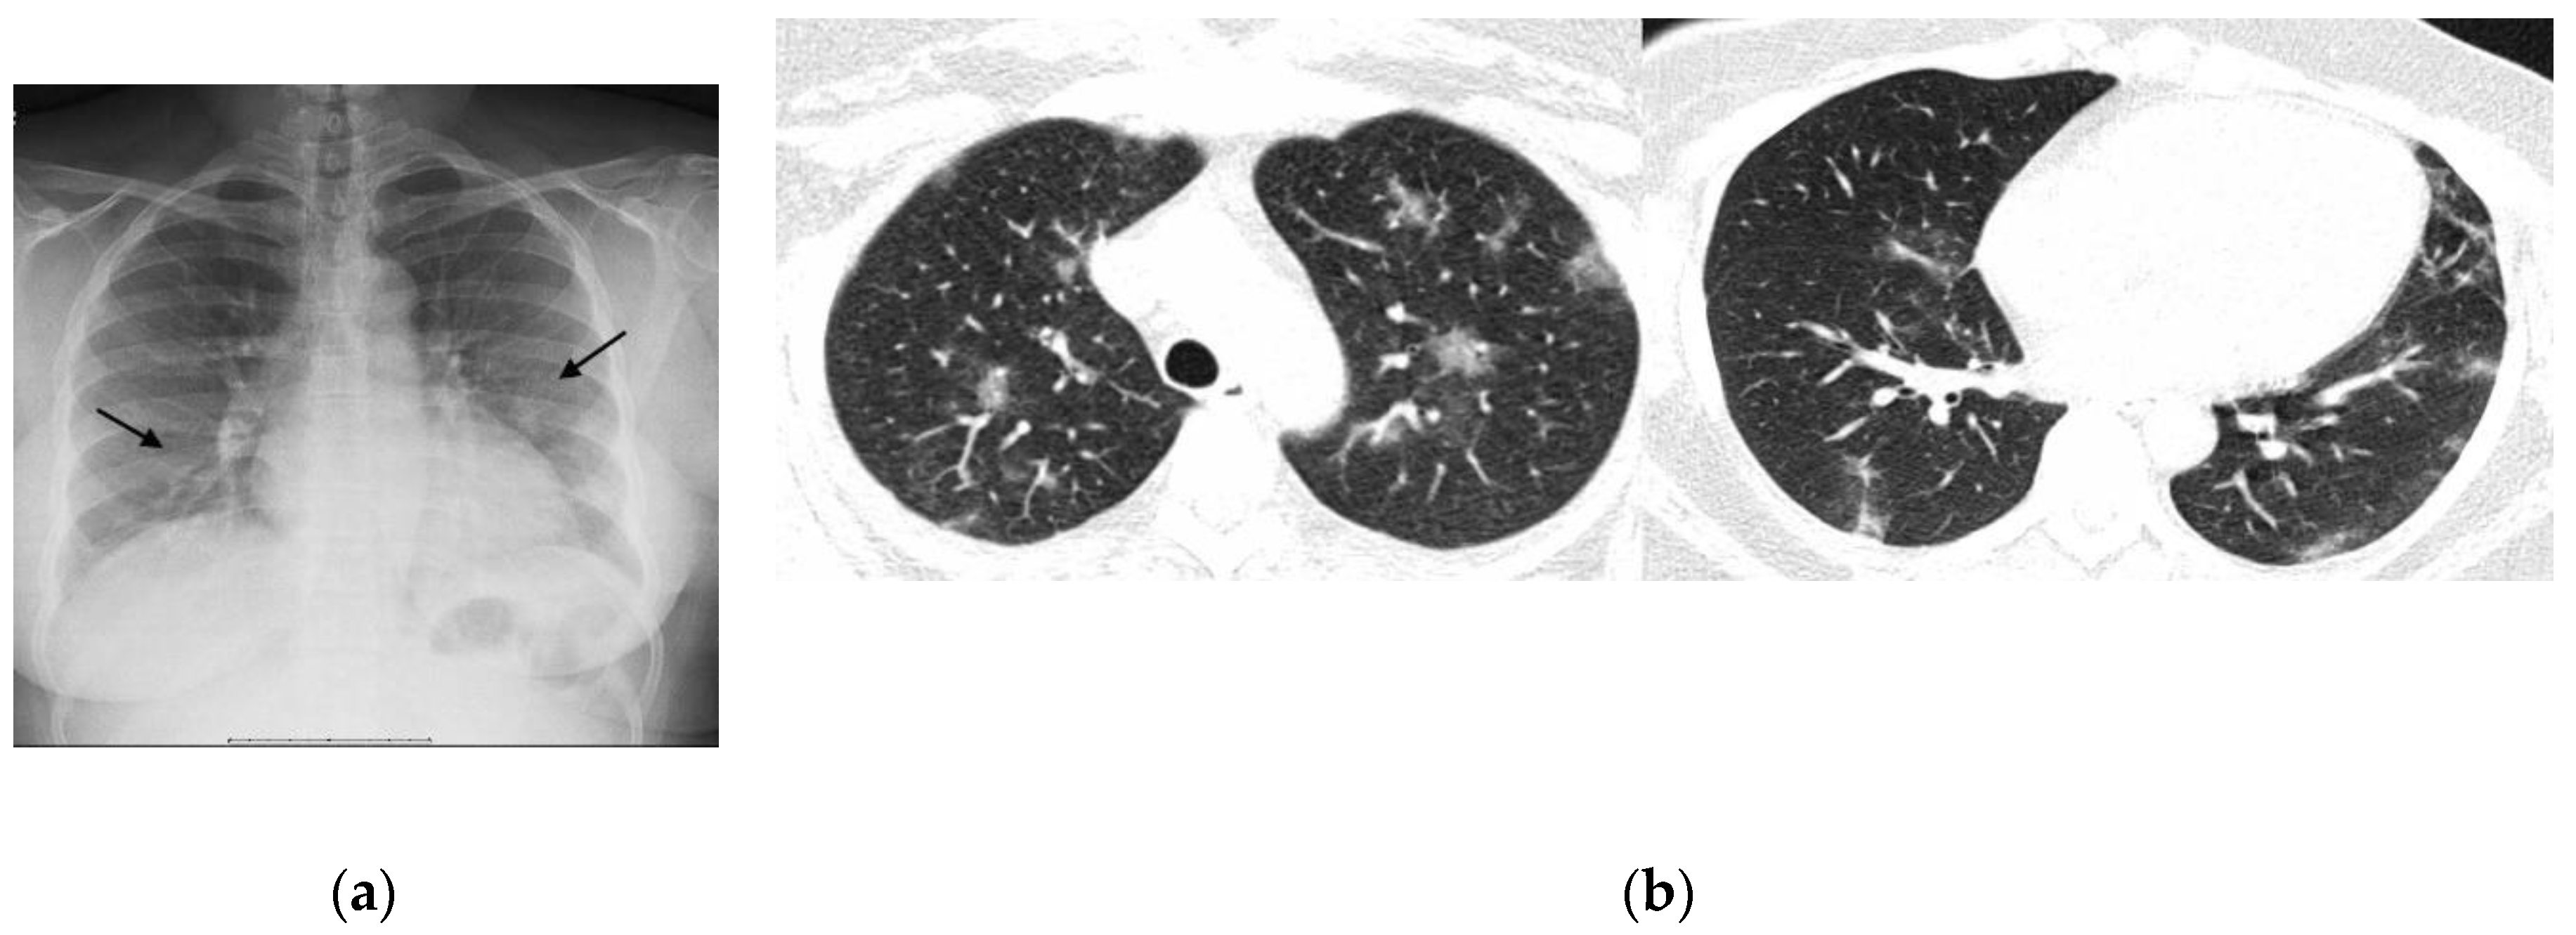

- Typical: Multifocal peripheral or central areas without a clear definition of vascular structure contours (opacity type 1) or a significant and variable increase in parenchymal density with a hazy appearance (opacity type 2); consolidations (opacity type 3) may be present but are associated with one of the other opacities.

- Possible: Opacities without a multifocal pattern or opacities type 1 and 2 in only one lobe or the upper thirds of the lungs.

- Atypical: Absence of typical or possible patterns, along with the presence of one or more of the following findings: cavities or isolated lobar/segmental consolidation (resembling bacterial pneumonia); micronodules; signs of pulmonary congestion and pleural effusions; or extensive pleural effusions.

- Negative: No findings indicative of pulmonary diseases.